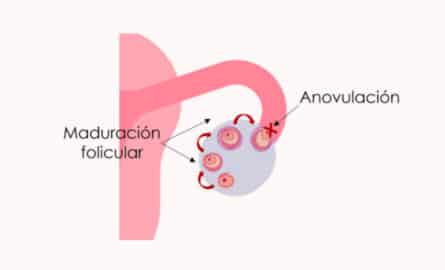

¿Qué es la anovulación y cómo afecta a la fertilidad?